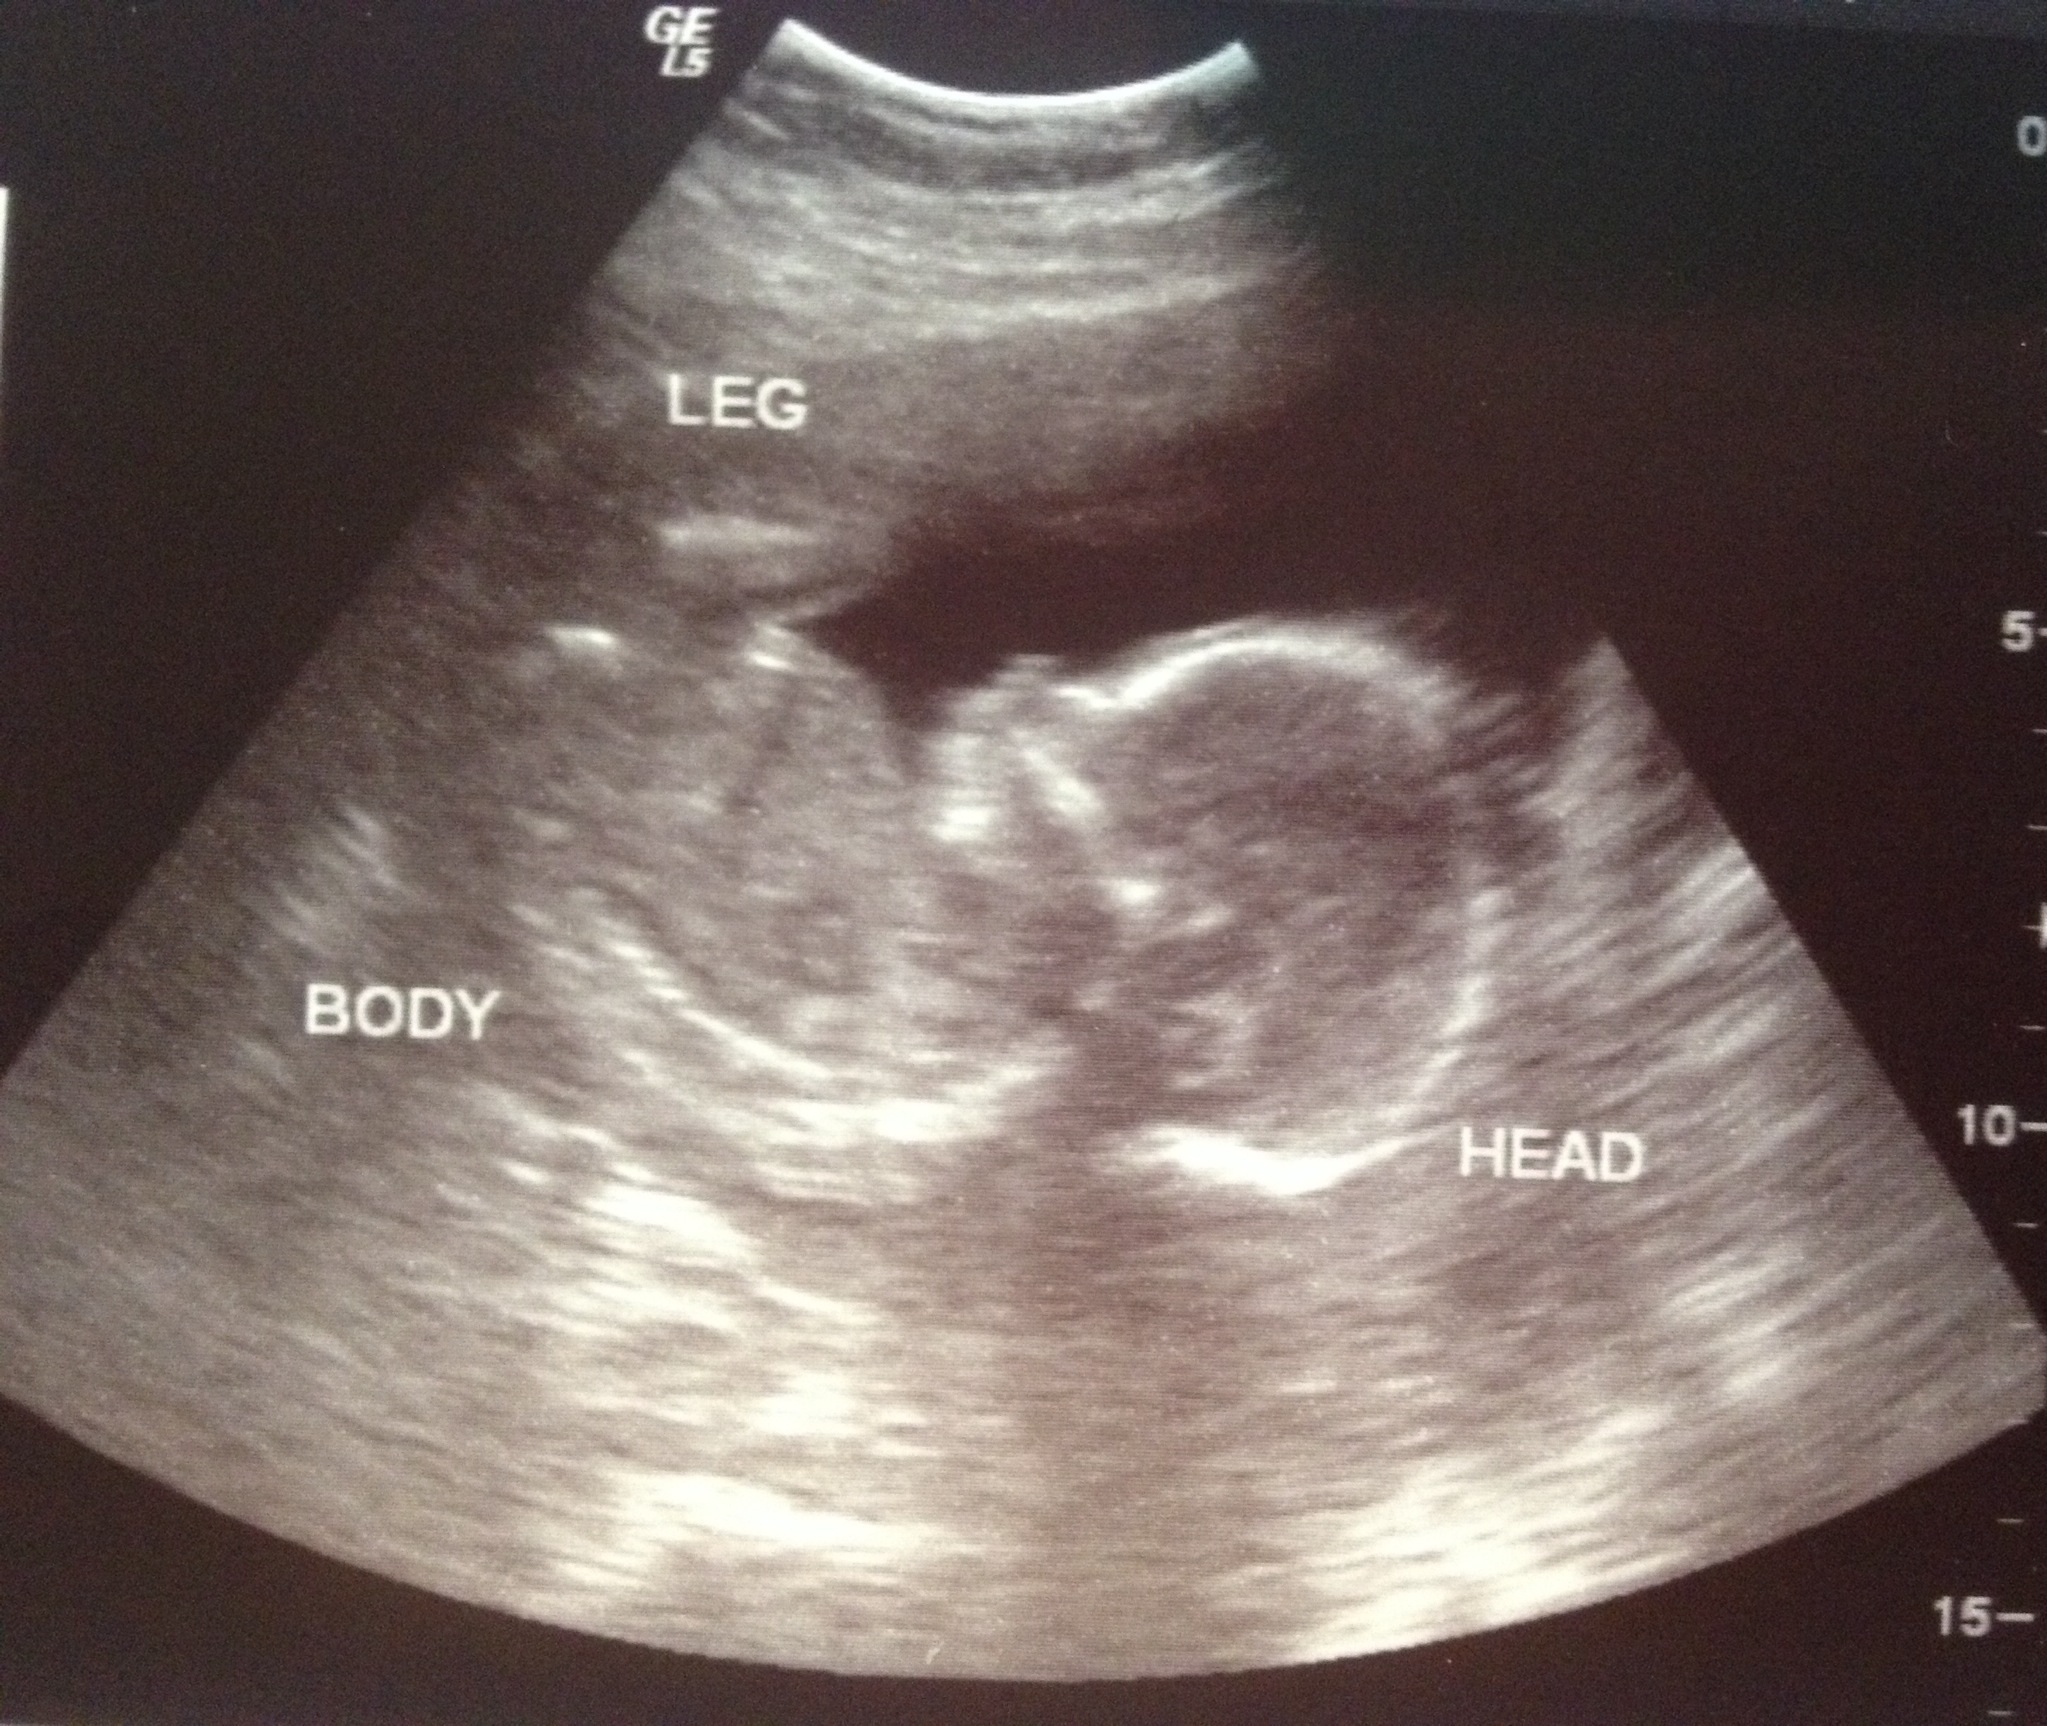

A girl!!!! My husband and I are ecstatic! We've already named her Katie

image.jpg